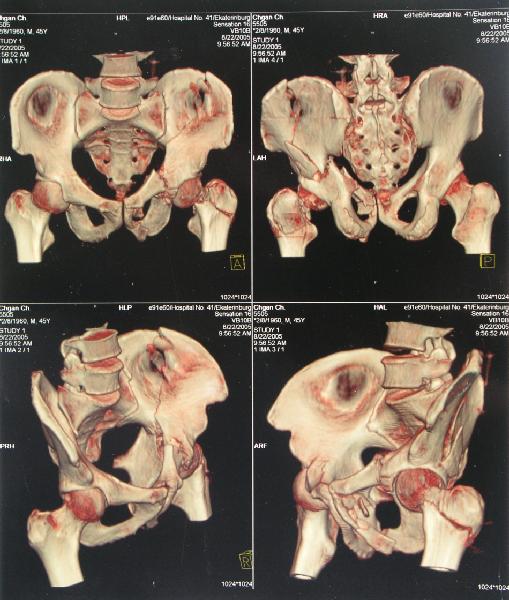

Случай, представленный Вами, совсем не идентичен обсуждаемому. У Вашего пациента был поперечный перелом с переломом заднего края, а в обсуждаемом случае - высокий двухколонный перелом вертлужной впадины.

То есть в представленном Вами случае был перелом заднего типа, в нашем случае центрального. У Вашего больного был застарелый задний вывих, у нашего - перелом шейки. Столь раннее разрушение головки, вероятно, было во многом обусловлено тем, что не была достигнута анатомическая репозиция, головка бедра осталась смещенной кзади, что является частой ошибкой при крупных фрагментах свода.

Необходимость фиксации вертлужной впадины в нашем случае вообще под вопросом, так как конгруэнтность сохранена (вторичная конгруэнтность типична для двухколонных переломов).

Наш больной пока обследуется, сделали сегодня КТ наконец-то.

Today CT was performed.

Сегодня КТ сделали.